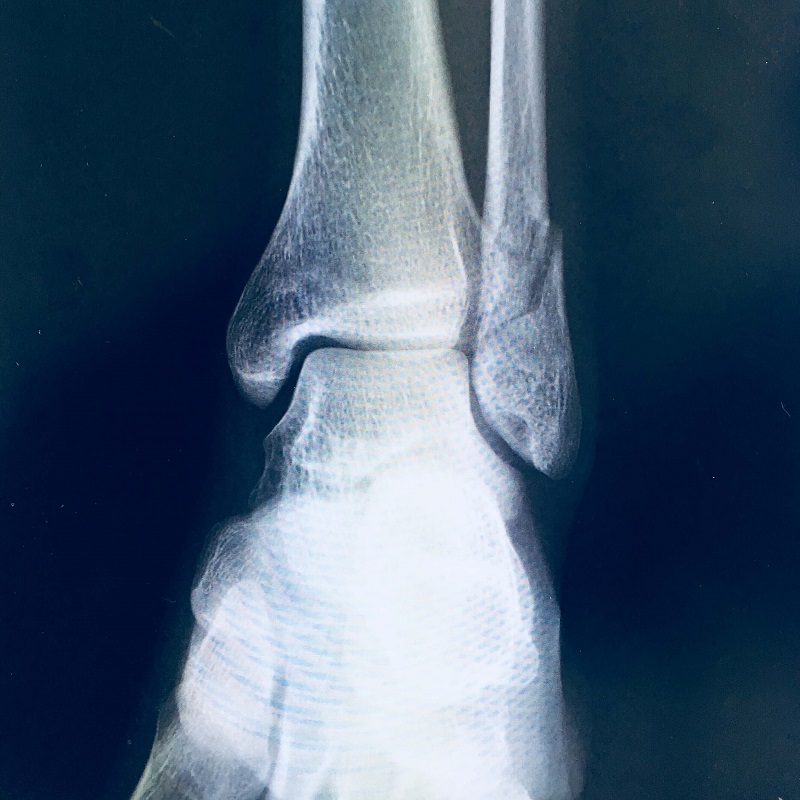

足首を骨折したのですが、もう歩けるの?

皆さんは松葉杖でギブスしたイメージかもしれませんが、

ギブスの代わりに金属プレートを埋め込んだのです。

手術後は何があったかはわかっていませんでしたが、

このX線を見て、なんだか痛みを感じるような気がします。